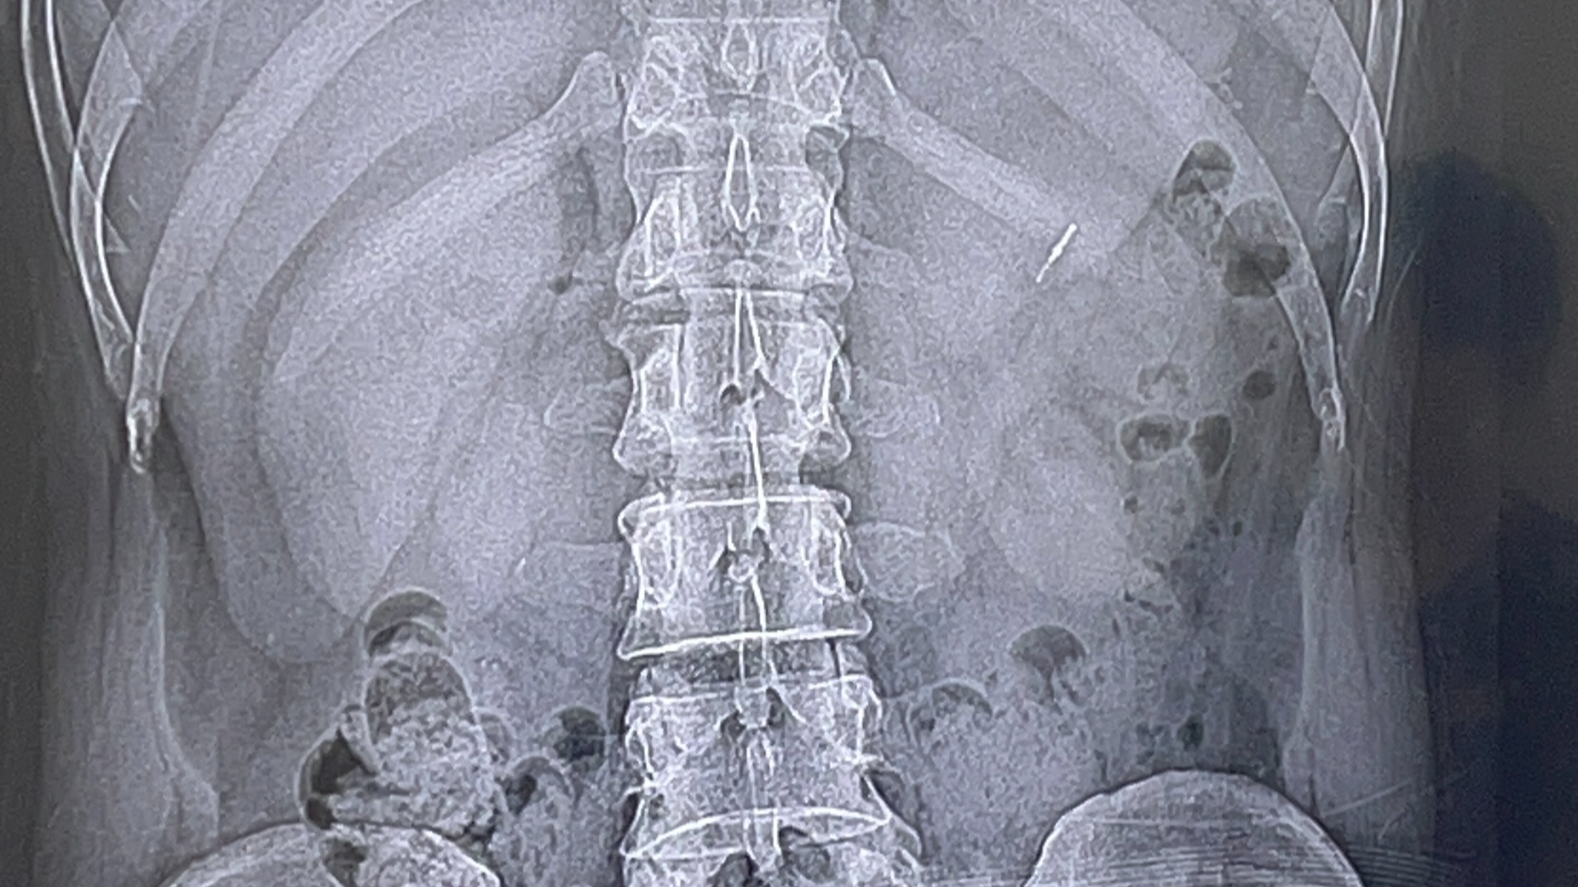

우연치않게 허리 사진을 찍어보다가 발견된 이상한 물질 정형외과 의사선생님이 최근에 대장 내시경 한적이나 치과치료 한적이 있냐고 물어본다. 폐 앞쪽으로 가슴쪽에 이상한? 물질이 찍혀있

의사샘이 사진을 보여주신다.

대장이 아니고 위에 있습니다!!

이전에 어딘가에서 위내시경하고 용종떼고 지혈하려 막아둔것입니다!

이제껏 그냥 사셨으니 그냥 사셔도 됩니다!